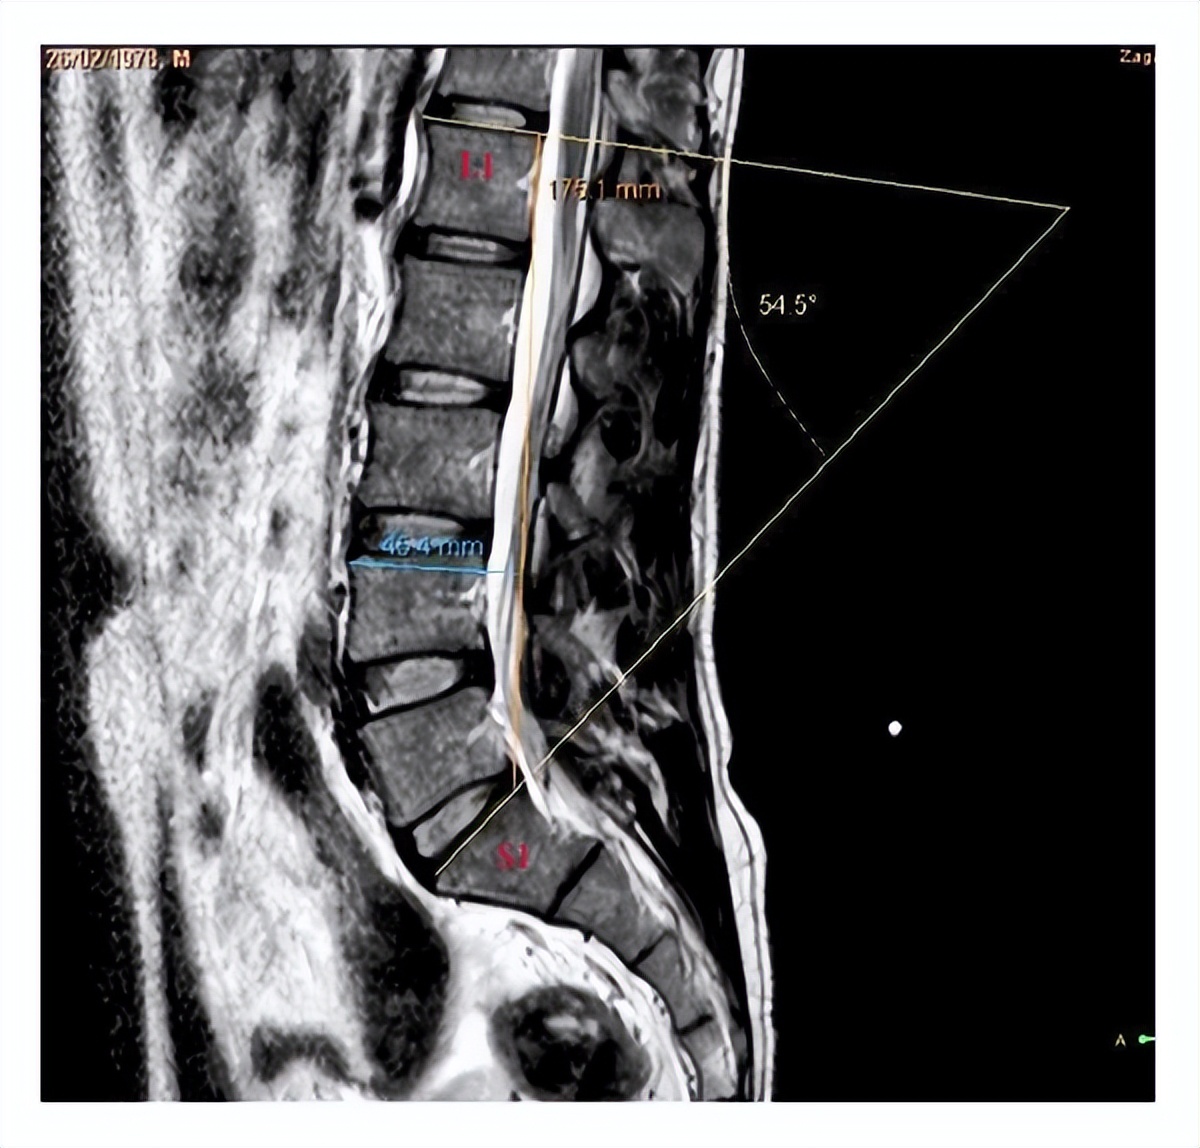

当然除了骨折之外 , 一些其他骨科疾病可能也需要用到金属内固定物 , 比如:腰椎和颈椎的相关疾病 , 也可能需要用到金属固定物 。